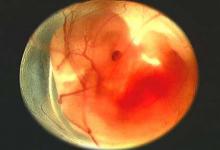

در یک عمل جراحی نادر توسط تیم جراحی بیمارستان دکترشیخ مشهد، جنینی از شکم نوزاد دو ماهه خارج شد.

خارج شدن یک جنین از شکم یک کودک دو ماهه!

به گزارش کورنگ، روابط عمومی دانشگاه علوم پزشکی مشهد، سرپرست تیم جراحی بیمارستان دکتر شیخ مشهد گفت: این نوزاد دو ماهه با مشکلات تنفسی، اتساع شکم و با تشخیص توده شکمی به بیمارستان منتقل شد که بررسی ها نشان داد جنینی در شکم کودک قرار دارد.

دکتر مرجان جودی افزود: این پدیده نادر تاکنون بیشتر در چند قلو زایی و قل های به هم چسبیده گزارش شده است.

این فوق تخصص جراحی کودکان اظهار کرد: در سونوگرافی مادر این کودک در دوران بارداری چهار قلو تشخیص داده شده بود که هنگام زایمان سه نوزاد متولد شدند.

جودی گفت: هم اکنون این کودک با حال عمومی مناسب در بخش مراقبتهای ویژه بیمارستان دکتر شیخ مشهد بستری است.

به گفته وی، وزن کودک پس از عمل جراحی و با خارج شدن جنین، از دو کیلو و 150 گرم به یک کیلو و 800 گرم کاهش یافت.

عضو هیات علمی دانشگاه علوم پزشکی مشهد افزود: اینگونه موارد اغلب در چند قلو زایی و یا افرادی که از داروهای محرک باروری استفاده کرده اند، مشاهده می شود.